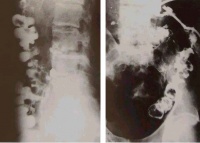

(二)骨形改变。管状长骨的破坏可表现为不同程度的膨胀变形,脊椎的椎体结核、椎体坍塌可呈楔状变形,椎体上下之间相互嵌入出现驼背或龟背畸形等。

(三)关节改变。关节软骨被破坏可使关节间隙狭窄,软骨破坏后不会再生,狭窄发生后会长期存在。脊椎椎间盘破坏不能再生,如破坏明显,椎间隙永久性消失

脊柱是骨结核最常见的发病部位,尤其是在老年人群;但是在发展中国家,儿童和青少年发病的也很常见。有些病人能发现肺或泌尿系有原发结核病灶,也有些病人找不到原发灶。淋巴和血行播散的结核一般发生在胸腰段,很少播散到颈椎和骶骨。脊柱结核的活动性病变破坏特定的椎体节段:通常是相临的两个椎体和椎体之间的间盘。一些研究者推测,病变破坏的这种特点的原因是:该部位动静脉血供丰富,而结核杆菌需要高的氧分压。

约80%的病人为间盘周围病变,侵及椎体前部,最后经韧带下间隙(前纵韧带)发展到相临的椎体。少数病人病变发生在椎体中央,这种病变可类似肿瘤或者引起明显的脊柱畸形,有时很难诊断。病人可能会有髓内肉芽肿、蛛网膜炎、椎体节段性塌陷形成的前方楔形变、驼背(Pott病)等。单纯的脊柱后部结构结核很少见。有时会形成椎旁脓肿并形成皮肤窦道,侵及同一平面的腹腔脏器。椎旁脓肿最远可到达腘窝。病人会有疼痛、无力,到晚期会出现截瘫。